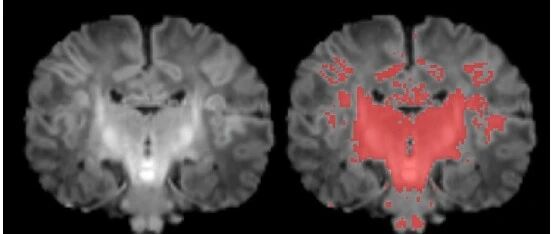

Environment International:揭开产前空气污染对新生儿大脑成熟的影响